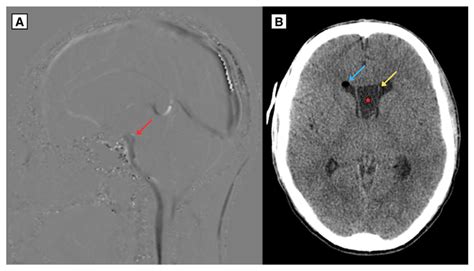

Diagnostic imaging techniques, such as magnetic resonance imaging (MRI), are essential for visualizing the Cavum Septum Pellucidum and assessing its size and shape. MRI provides high-resolution images of the brain, allowing clinicians to detect abnormalities in the Cavum Septum Pellucidum and other structures.

| Computed Tomography (CT) | Uses X-rays to create cross-sectional images of the brain | Less commonly used for Cavum Septum Pellucidum assessment |

MRI is the preferred imaging technique for evaluating the Cavum Septum Pellucidum due to its high resolution and ability to differentiate between soft tissues. CT scans and PET scans may also be used in specific clinical contexts, but they are less commonly employed for assessing the Cavum Septum Pellucidum.